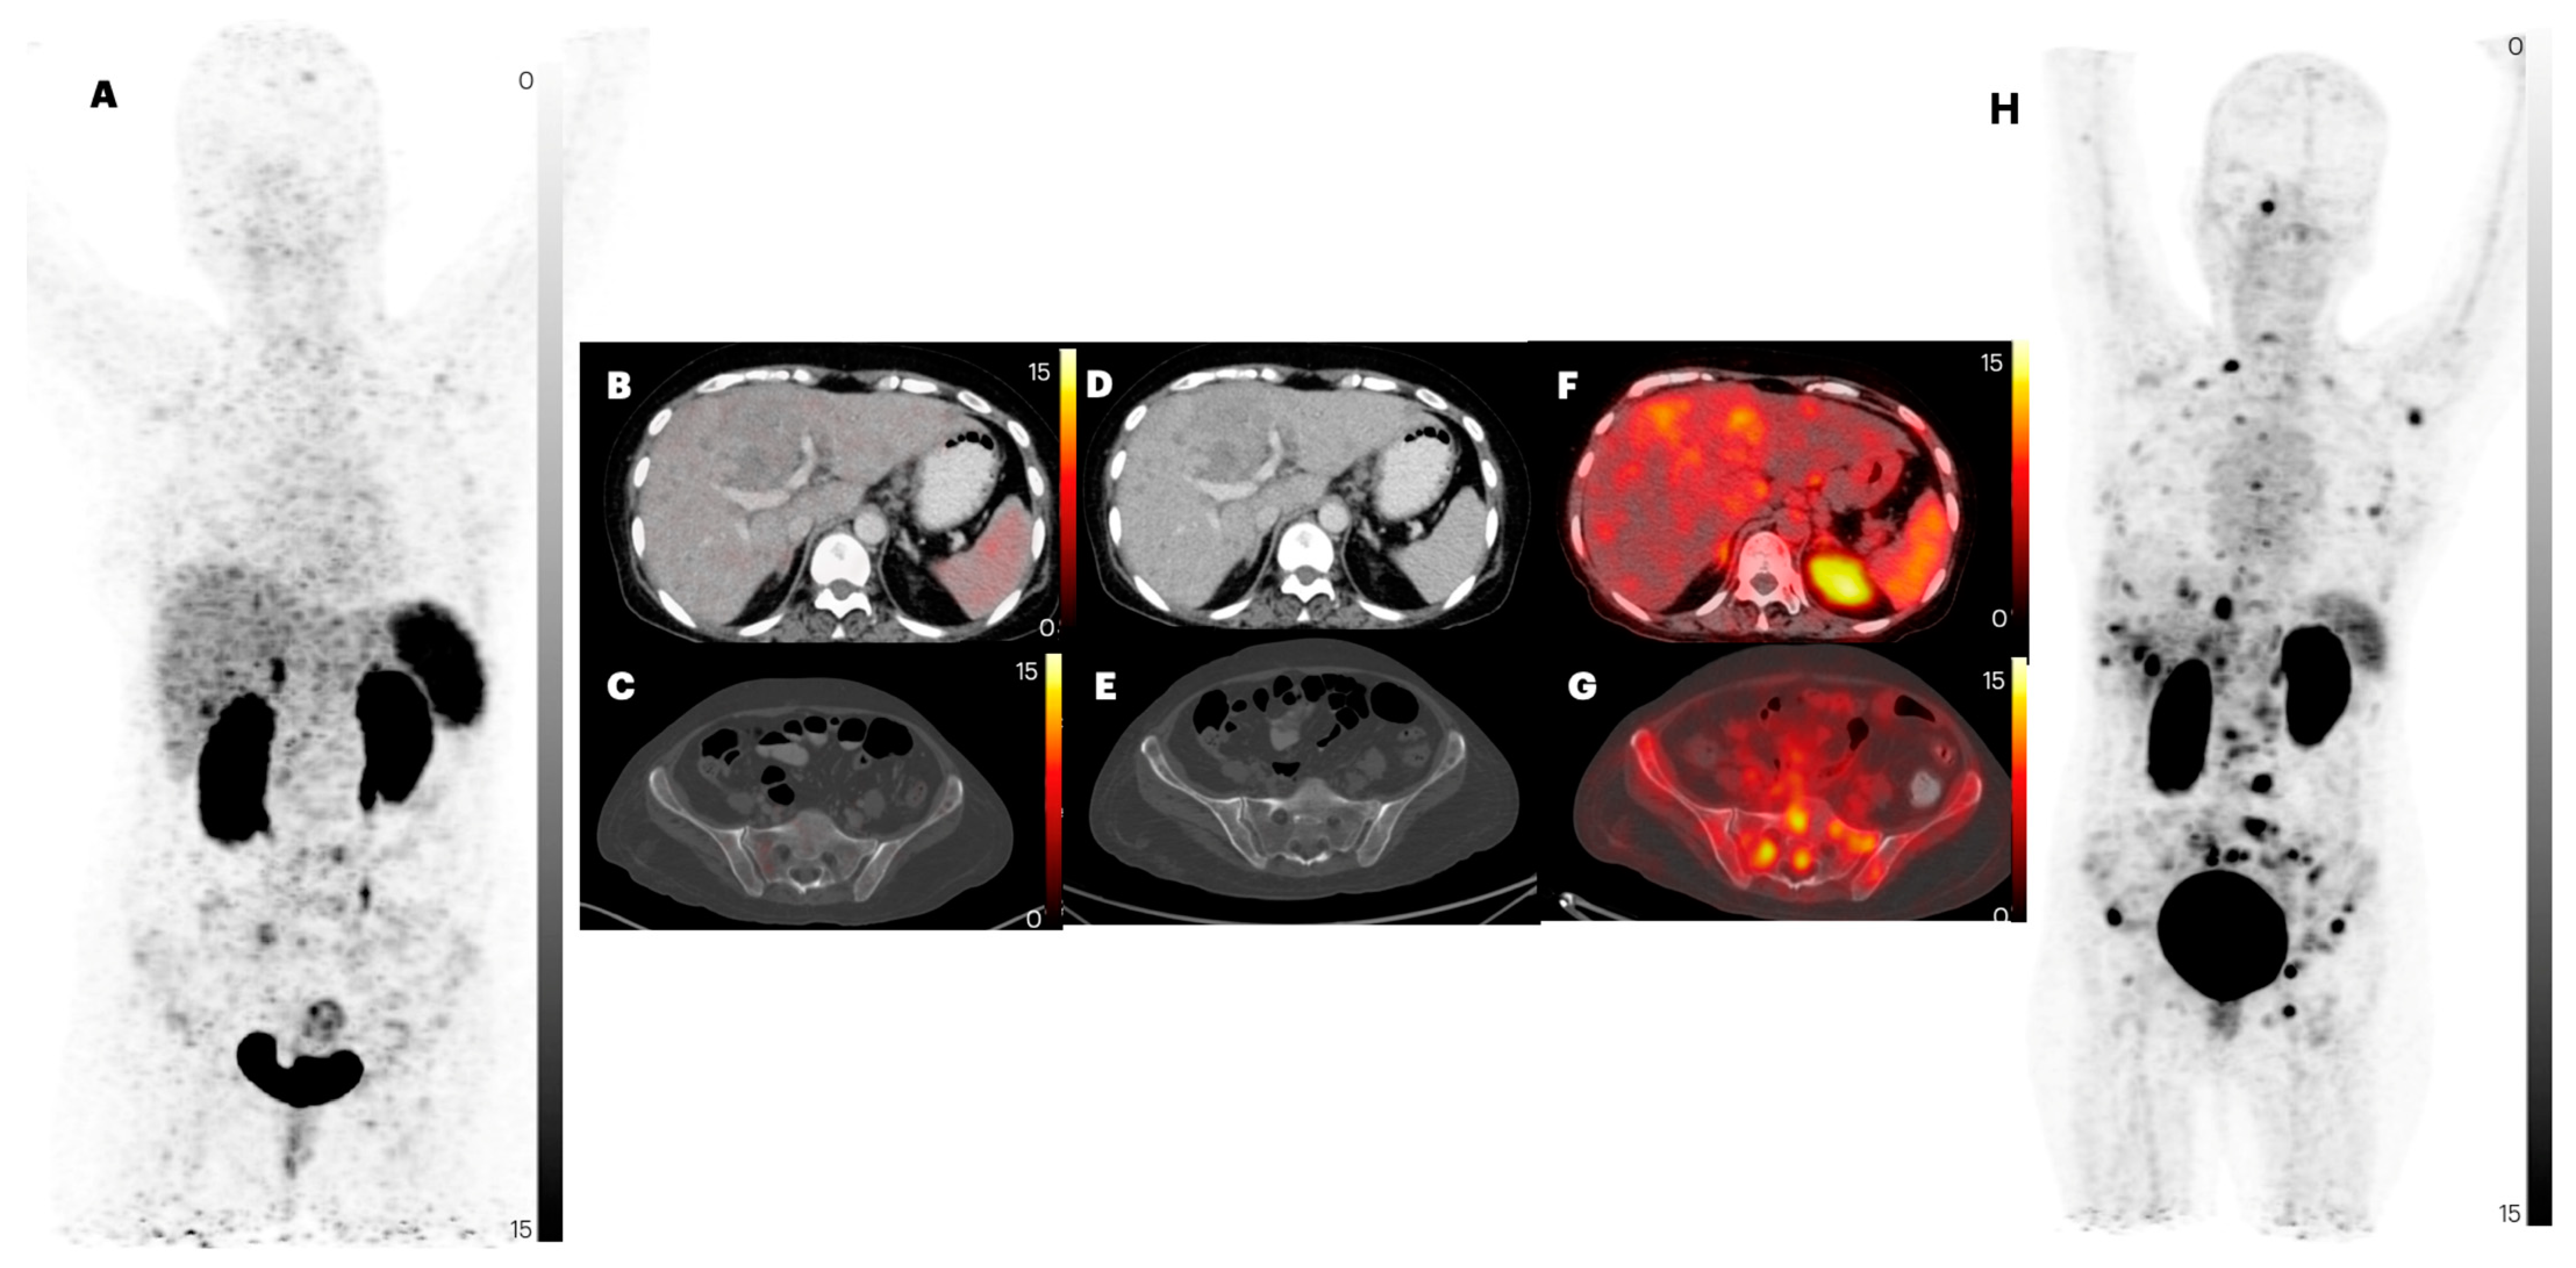

2.2. Comparison of Lesion Detection and Uptake between [68Ga]Ga-DOTANOC and [68Ga]Ga-DATA5m-LM4

2.2.4. Liver Metastases